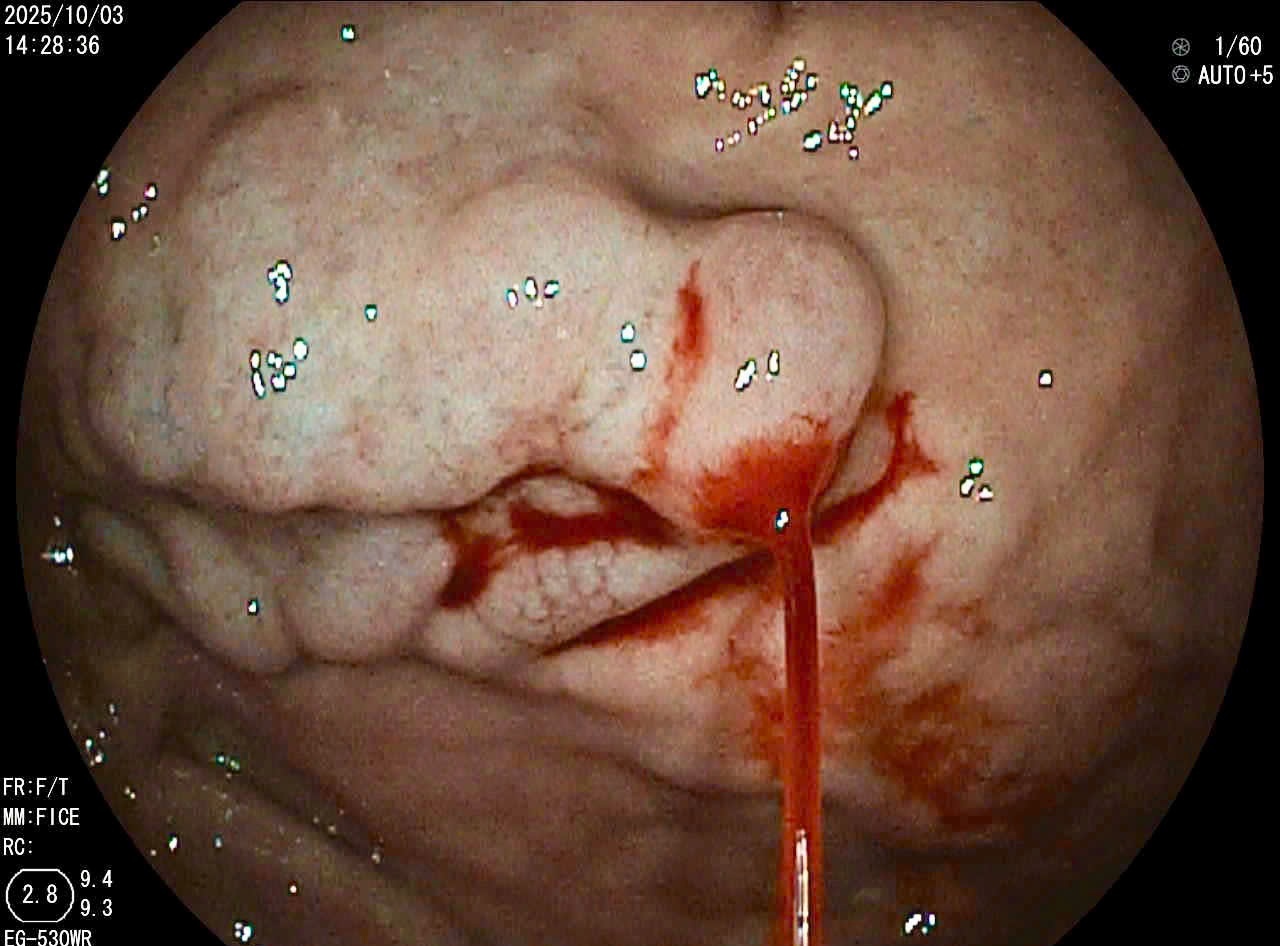

• Bệnh lý về đáy mắt: Đây là những tổn thương nằm sâu bên trong mắt mà chỉ có các bác sĩ nhãn khoa, với sự hỗ trợ của trang thiết bị chuyên dụng, mới có thể phát hiện được. Cha mẹ hoàn toàn không thể nhận biết bằng mắt thường.